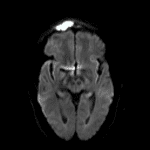

- Expansile lesion in the right frontal sinus with peripheral enhancement and central restricted diffusion measuring 3.5 x 2 x 2.5 cm

- Overlying thin peripherally-enhancing subgaleal collection along the superior margin of the frontal lesion with associated restricted diffusion and T2 signal hyperintensity and enhancement in the right frontal scalp

Expansile lesion in the right frontal sinus with peripheral enhancement and central restricted diffusion measuring 3.5 x 2 x 2.5 cm. This appearance is concerning for a mucopyocele (infected mucocele). Associated mass effect on the subjacent right frontal lobe with associated dural thickening and enhancement but no discrete extraaxial collection or evidence of cerebritis.

Overlying thin subgaleal abscess (along the superior margin of the collection) and cellulitis.